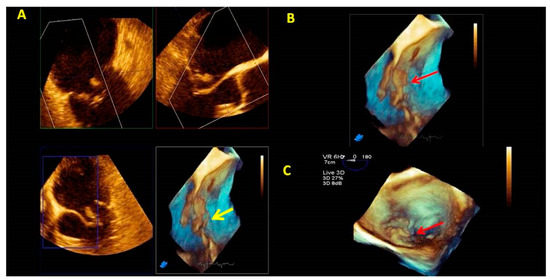

- Zoom mode: If zoom RT3DE is activated, two orthogonal 2D preview images show the ‘‘truncated’’ pyramid sector that the operator can move over the region of interest, regulating width and length and preventing respiratory or rhythm artifacts. However, it is limited by a low temporal resolution that can be improved by minimizing the sector’s width and length. (Figure 2B).

- “Full volume multiple beat” with or without color Doppler. This modality implies an electrocardiogram (ECG) synchronization permitting the analysis of an extensive volumetric data set by acquiring narrow subvolumes (two-seven sequential cardiac cycles). High spatial and temporal resolutions and a global MV view with excellent image quality represent the greatest strength of this modality (Figure 2C).